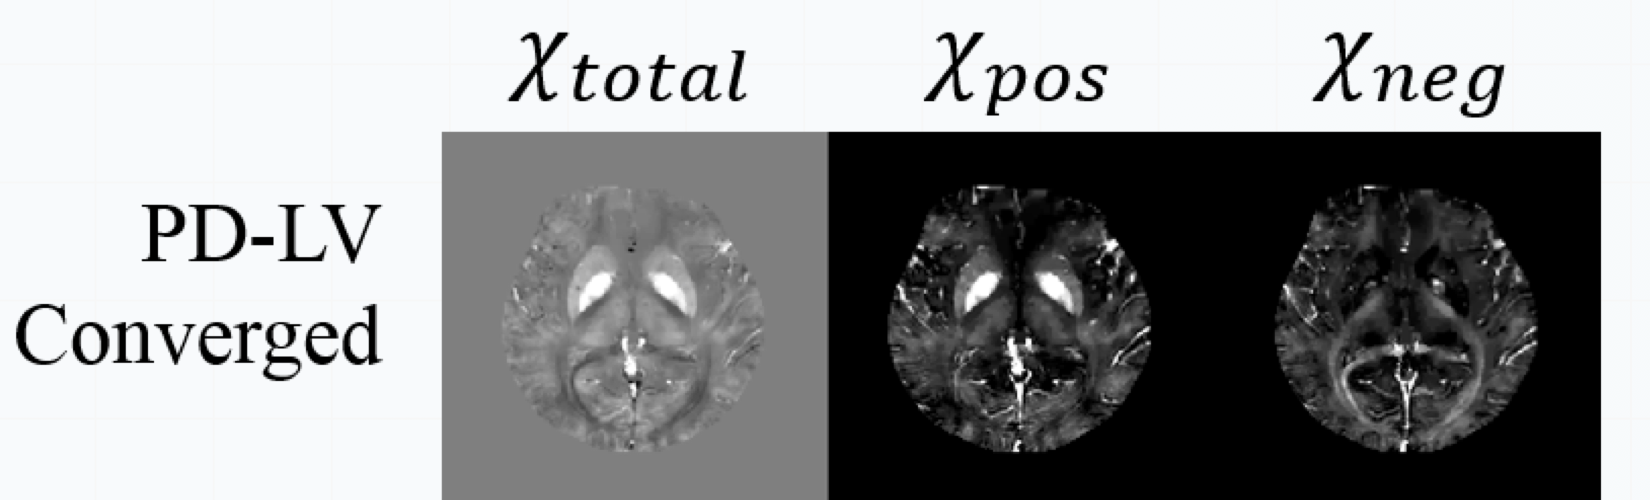

Also used in fast medical imaging:

Fast and accurate reconstruction for susceptibility source separation in QSM”, Seyoon Ko, Jingu Lee, Joong-Ho Won, and Jongho Lee, ISMRM 2018.